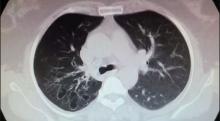

A 54-year-old woman was admitted to the author’s clinic with complaints of a cough producing bloody sputum for the past six months. No etiological factors had been detected during medical examinations. Chest-computed tomography showed localized bronchiectasis in the right upper lobe, and it was recommended that the patient undergo a VATS lobectomy.